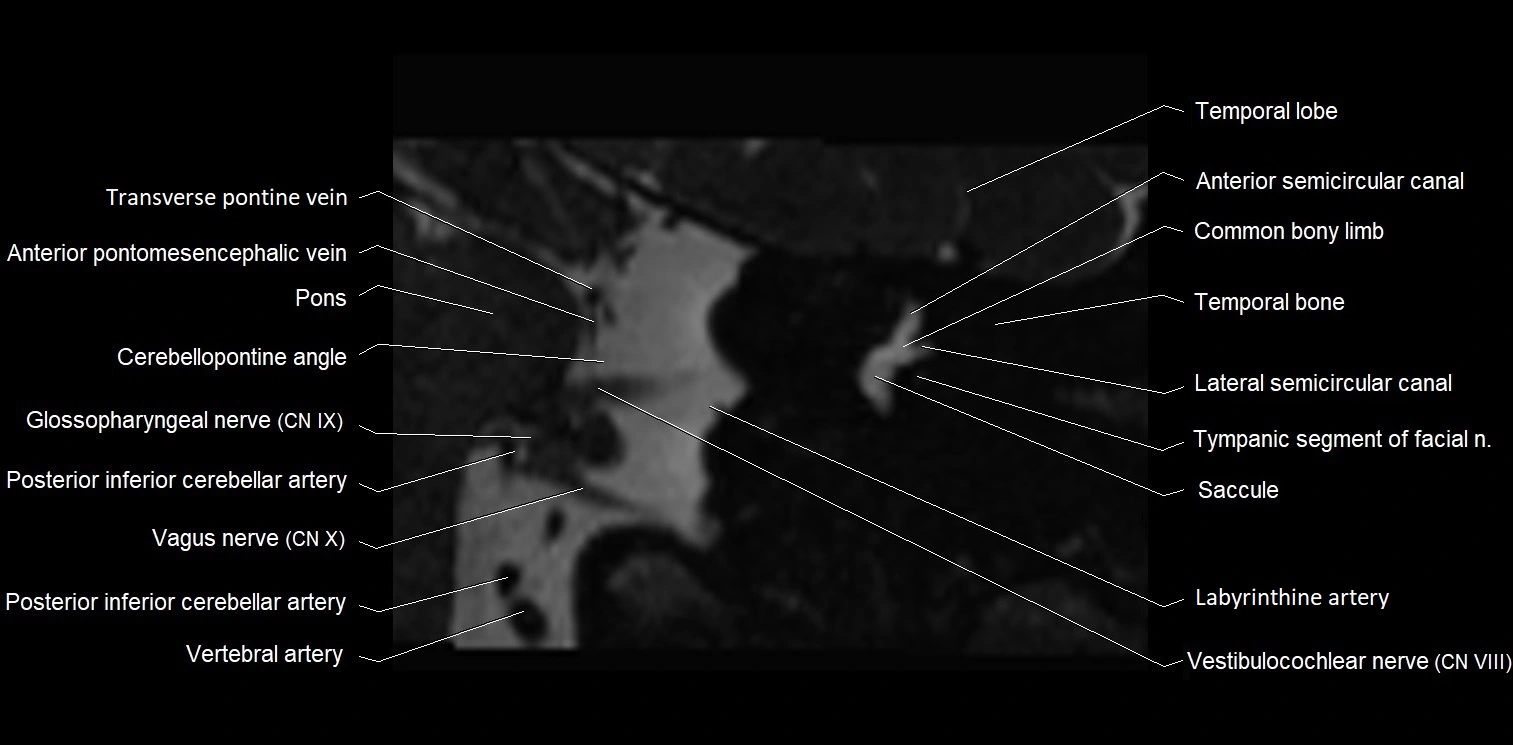

MRI Appearance

• The abducens nerve is a small, thin, linear structure

• Best visualized on high-resolution T2-weighted 3D MRI sequences (e.g., FIESTA or CISS)

• Seen as a hypointense (dark) line running from the brainstem at the pontomedullary junction, traversing the prepontine cistern, and entering Dorello’s canal under the petrosphenoidal ligament, then into the cavernous sinus, and finally the orbit

• May be challenging to visualize in standard MRI due to its small size

• Pathology may be inferred by absence, displacement, or enhancement of the nerve